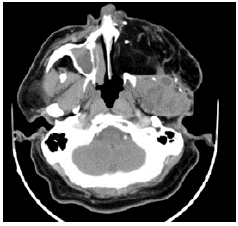

Eleven years after the initial surgery, and after 3 surgeries, a new local relapse was discovered. On physical examination, the patient was found in good condition, with left facial palsy and mass in left masticator space with extension to hard and soft palate, in addition to left submandibular ganglion conglomerate. Contrasted CT showed a mass that involved the left masticator space, lobed, of heterogeneous density with extension towards the skull and average cranial fossa of 36.7x53.6x42mm in anteroposterior section (Figures 3 and 4); biopsy and histopathological study confirmed ameloblastoma.

Computed tomography of paranasal sinuses with evidence of heterogeneous and hypotensive mass in the left masticator space of lobed contours with dimensions of 36.7x53.6x42.7mm.

Figure 3: Computed tomography of paranasal sinuses with evidence of heterogeneous and hypotensive mass in the left masticator space of lobed contours with dimensions of 36.7x53.6x42.7mm.

Source: Document obtained during the study.